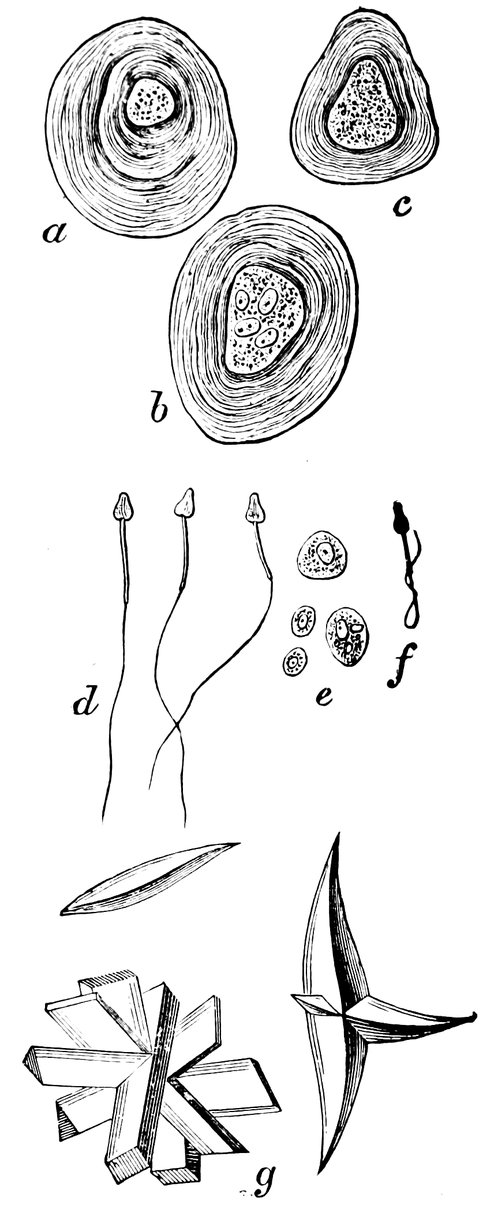

| 61. | a. b. c. Prostatic calculi from normal semen, d. Spermatozoa. e. Large and small cells, some containing granules, as morphological elements of semen. f. Spermatozoon distorted by imbibition of water. g. Crystals (after Bizzozero) | 311 |

| 62. | Normal Semen | 311 |

| 63. | Semen consisting chiefly of sperm-crystals, cylindrical epithelium, and small granules exhibiting molecular movement—but containing no spermatozoa | 315 |

| 64. | Oligozoöspermia. a. Living Spermatozoa, b. Dead Spermatozoa, c. Pus Corpuscles, d. Erythrocyte, e. Seminal granules | 317 |